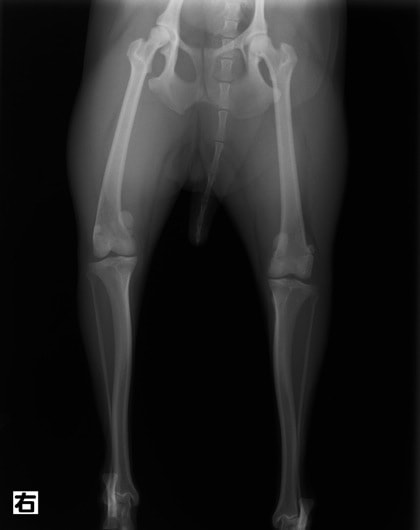

■ 症例20 ポメラニアン 8ヶ月 1.8kg

左右膝蓋骨脱臼 グレードⅢ

2ヶ月前から間欠的跛行が認められ、両膝の膝蓋骨脱臼整復術を行った。

手技は縫工筋及び内側広筋の解放、脛骨粗面の外側転位、滑車ブロック形造溝術、内外側関節包の縫縮を選択し実施した。

右側の膝蓋骨脱臼は上記手技で整復されたものの、左側はそれのみでは膝蓋骨が浮く様子が認められた。その為、PDS縫合糸にて膝蓋靱帯を1糸のみ縫合し、靱帯の縫縮を行った。

膝蓋骨脱臼は膝関節における膝蓋骨の内外側の脱臼と定義されるが、時として単純な内外の脱臼ではなく、膝蓋骨が大きく前方に浮き上がるように脱臼する場合がある。特にトイプードルやポメラニアンといった犬種に多く認められる。

内側脱臼に加えて前方への浮き上がりを矯正する為に、従来より脛骨粗面転移により膝蓋靭帯を外方と下方に引っ張り、固定する方法を選択する。膝蓋骨の前方への浮き上がりが軽度の場合は、従来法ではなく関節包の縫縮で対応していた。しかし、一部の症例で膝蓋骨の動きが悪くなり伸展機構が円滑に機能せずロボット様歩行になるケースがあった。

その為、膝蓋靭帯自体を縫縮する方法を採用した。この方法により、膝関節の伸展機構を妨げず膝蓋骨の軽度の浮きを矯正することが可能となった。

本症例の経過は良好である